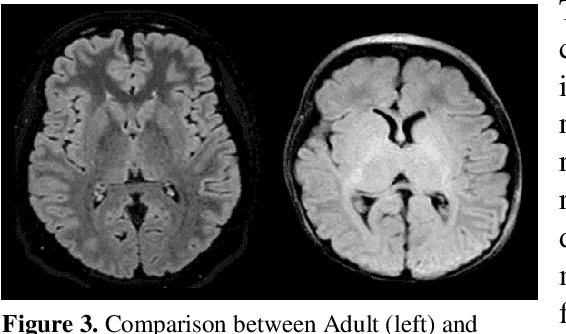

Abstract:This paper presents a deep learning framework for image classification aimed at increasing predictive performance for Cytotoxic Edema (CE) diagnosis in infants and children. The proposed framework includes two 3D network architectures optimized to learn from two types of clinical MRI data , a trace Diffusion Weighted Image (DWI) and the calculated Apparent Diffusion Coefficient map (ADC). This work proposes a robust and novel solution based on volumetric analysis of 3D images (using pixels from time slices) and 3D convolutional neural network (CNN) models. While simple in architecture, the proposed framework shows significant quantitative results on the domain problem. We use a dataset curated from a Childrens Hospital Colorado (CHCO) patient registry to report a predictive performance F1 score of 0.91 at distinguishing CE patients from children with severe neurologic injury without CE. In addition, we perform analysis of our systems output to determine the association of CE with Abusive Head Trauma (AHT) , a type of traumatic brain injury (TBI) associated with abuse , and overall functional outcome and in hospital mortality of infants and young children. We used two clinical variables, AHT diagnosis and Functional Status Scale (FSS) score, to arrive at the conclusion that CE is highly correlated with overall outcome and that further study is needed to determine whether CE is a biomarker of AHT. With that, this paper introduces a simple yet powerful deep learning based solution for automated CE classification. This solution also enables an indepth analysis of progression of CE and its correlation to AHT and overall neurologic outcome, which in turn has the potential to empower experts to diagnose and mitigate AHT during early stages of a childs life.